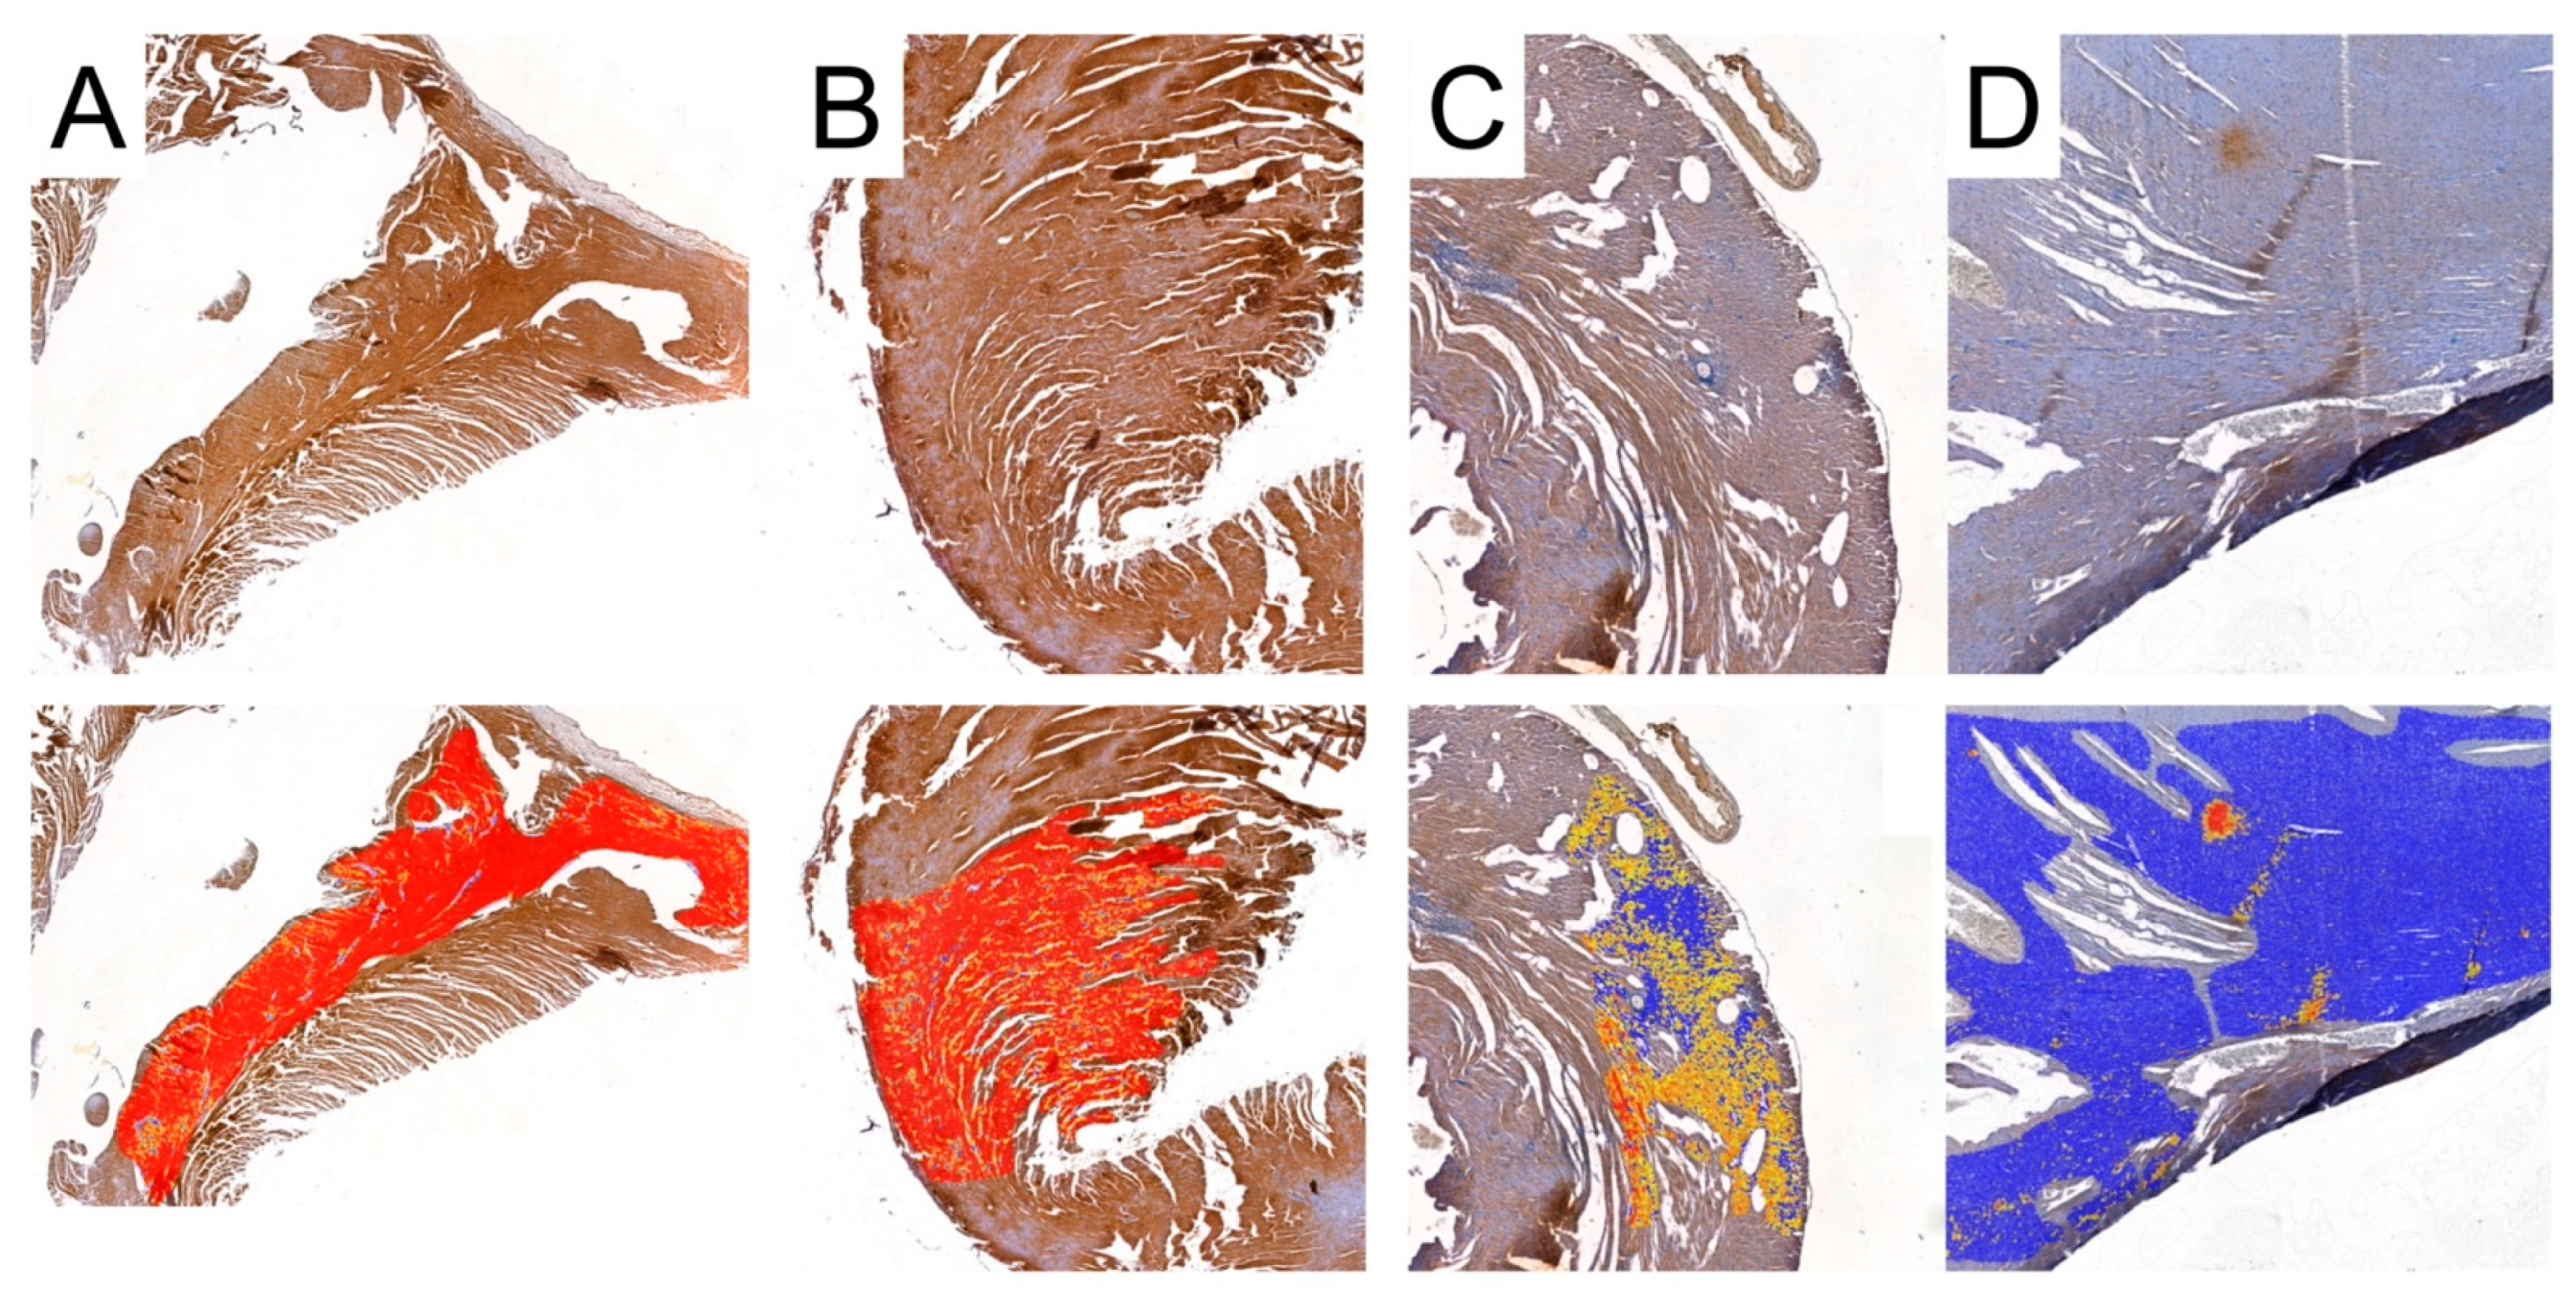

3.5. Digital Analysis of Immunolocalization of the MMP-2/TIMP-2